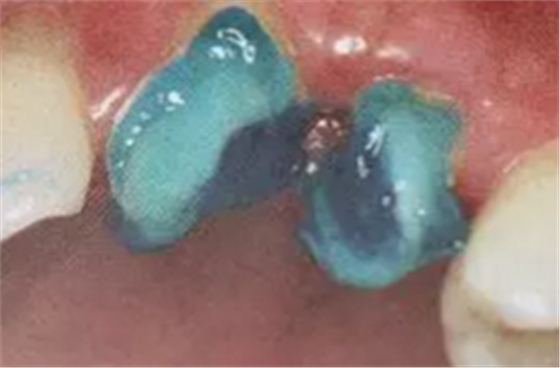

(根管內(nèi)殘留物)

個(gè)人見解:必要的情況下先開闊根管口建立一定的視角后,慢速手機(jī)上G鉆為引導(dǎo)鉆,由號遞增引導(dǎo)開闊通路;P鉆預(yù)備樁道,同樣需要由小向大號遞增,直到選擇好適合的號預(yù)備到規(guī)定測量的深度即可,再配合纖維樁系統(tǒng)中各型號纖維樁所匹配的樁道鉆,預(yù)備、修整成與纖維樁相適應(yīng)的樁道。

預(yù)備后根管壁上會(huì)不同程度的牙膠和封閉劑等殘留物,所以樁道預(yù)備前后建議X線片輔助檢查預(yù)備深度等情況,而殘留物也會(huì)很清晰地顯現(xiàn)。

根管銼去除殘留物,很難去除干凈,而備取樁道時(shí),禁止使用牙膠溶解劑(如:丁克除、氯仿)等有機(jī)溶劑去除殘留物,以防破壞根尖區(qū)牙膠的封閉和防止附著根管壁影響粘接。

(超聲去除根管殘留物)

通常此時(shí)以超聲潔牙機(jī)更換較細(xì)工作尖進(jìn)入根管(根管消毒沖洗液配合清潔工作后面會(huì)提到),徹底去除樁道根管壁上的附著殘留物,效果明顯。再配合X線片、根管顯微鏡輔助檢查清理的情況下更佳。